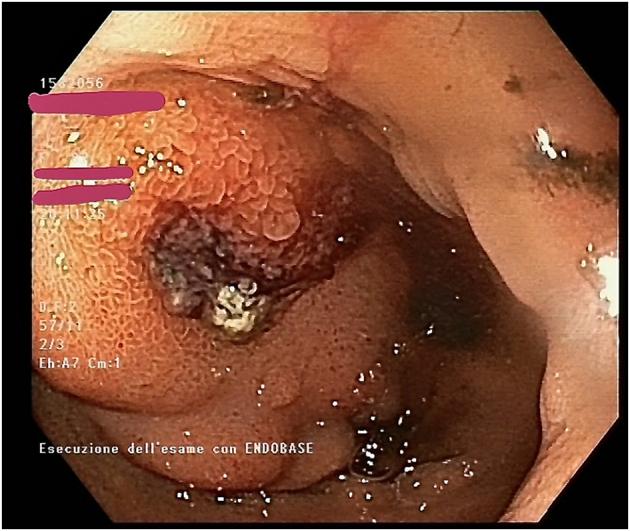

PRESENTATION OF CASE

We report the case of an 82-years-old female presenting with abdominal pain and hematemesis. Upper gastrointestinal endoscopy retrieved a large duodenal mass and subsequent CT scans identified a large GAA with contrast extravasation. Endovascular procedure included selective arteriography, microcatheterization, and embolization.

我们报告了一例82岁女性,表现为腹痛和呕血。上消化道内镜检查发现十二指肠有一个大肿块,随后的CT扫描确定为一个大的GAA并伴有造影剂外渗。血管内治疗包括选择性动脉造影、微导管插入和栓塞。